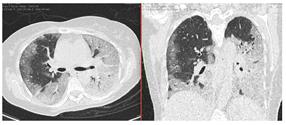

2. Наличие клинических проявлений, указанных в п. 1, в сочетании с характерными изменениями в легких по данным компьютерной томографии (КТ) (см. Приложение 1 настоящих рекомендаций) вне зависимости от результатов однократного лабораторного исследования на наличие РНК SARS-CoV-2 и эпидемиологического анамнеза.

- Изменения при КТ (рентгенографии), типичные для вирусного поражения (объем поражения минимальный или средний; КТ 1-2)

- Изменения в легких при КТ (рентгенографии), типичные для вирусного поражения (объем поражения значительный или субтотальный; КТ 3-4)

- Изменения в легких при КТ (рентгенографии), типичные для вирусного поражения критической степени (объем поражения значительный или субтотальный; КТ 4) или картина ОРДС.

КТ имеет высокую чувствительность в выявлении изменений в легких, характерных для COVID-19. Применение КТ целесообразно для первичной оценки состояния ОГК у пациентов с тяжелыми прогрессирующими формами заболевания, а также для дифференциальной диагностики выявленных изменений и оценки динамики процесса. КТ позволяет выявить характерные изменения в легких у пациентов с COVID-19 еще до появления положительных лабораторных тестов на инфекцию с помощью МАНК. В то же время, КТ выявляет изменения легких у значительного числа пациентов с бессимптомной и легкой формами заболевания, которым не требуется госпитализация. Результаты КТ в этих случаях не влияют на тактику лечения и прогноз заболевания при наличии лабораторного подтверждения COVID-19. Поэтому массовое применение КТ для скрининга асимптомных и легких форм болезни не рекомендуется.